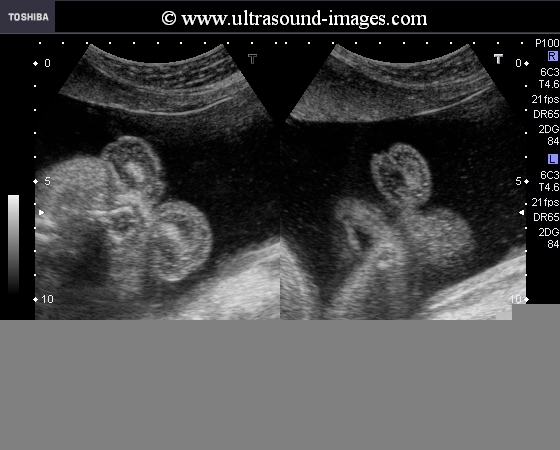

Icthyosis is a severe and very rare congenital anomaly seen in foetuses where there is marked thickening of the keratin in the skin resulting in certain typical appearances in the fetus. It can very often be lethal though there are reports of infants with icthyosis surviving to young adulthood. Icthyosis is also called Harlequin Icthyosis because of its typical appearances. Icthyosis means fishlike appearance due to the resemblance of the fetus to a fish. These ultrasound images show typical features of Harlequin Icthyosis:

1- bilateral ectropion resulting in bulbous orbits due to the eversion of the eyelids. The fetus in these ultrasound images shows bilateral orbital masses due to ectropion.

2-eclabion or eversion of the lips resulting in a constantly open mouth. After repeated imaging over a period of time, the mouth remained open all the time.

3- fixed flexion deformity of the limbs is a typical feature of Icthyosis

4- fusion of the digits is also seen in these ultrasound images

5- flat nose is also another feature seen in these images

6- often there is markedly echogenic amniotic fluid- not seen in these ultrasound images

These ultrasound images of Harlequin Icthyosis are courtesy of Dr Durr-e Sabih, FRCP, Pakistan.